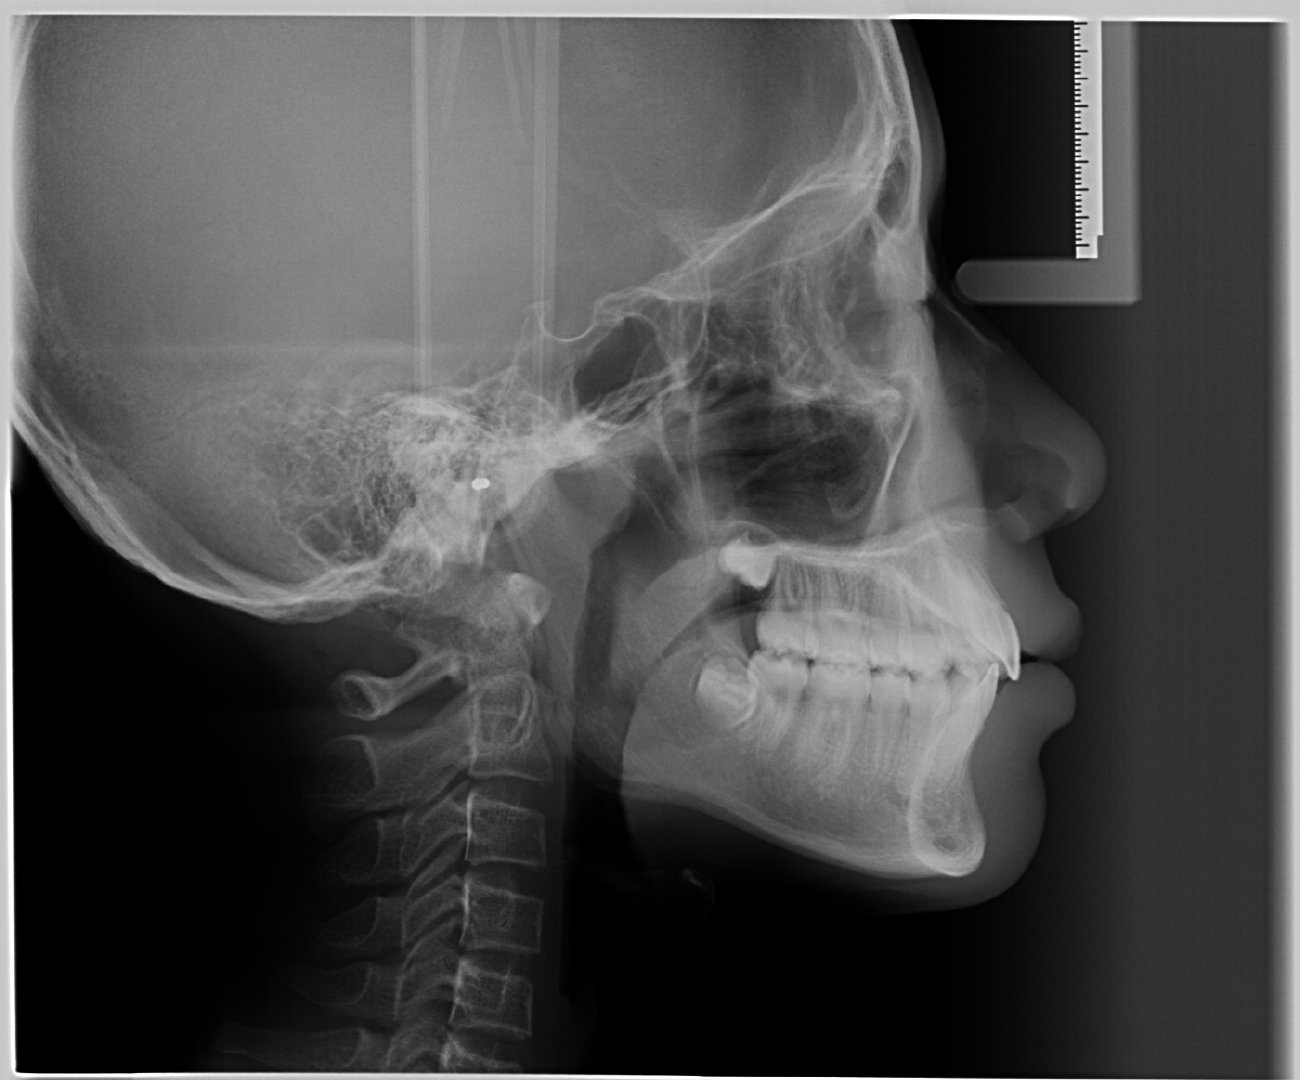

(1)拍摄两张x光片(包括全景片、侧位片)。

侧位片